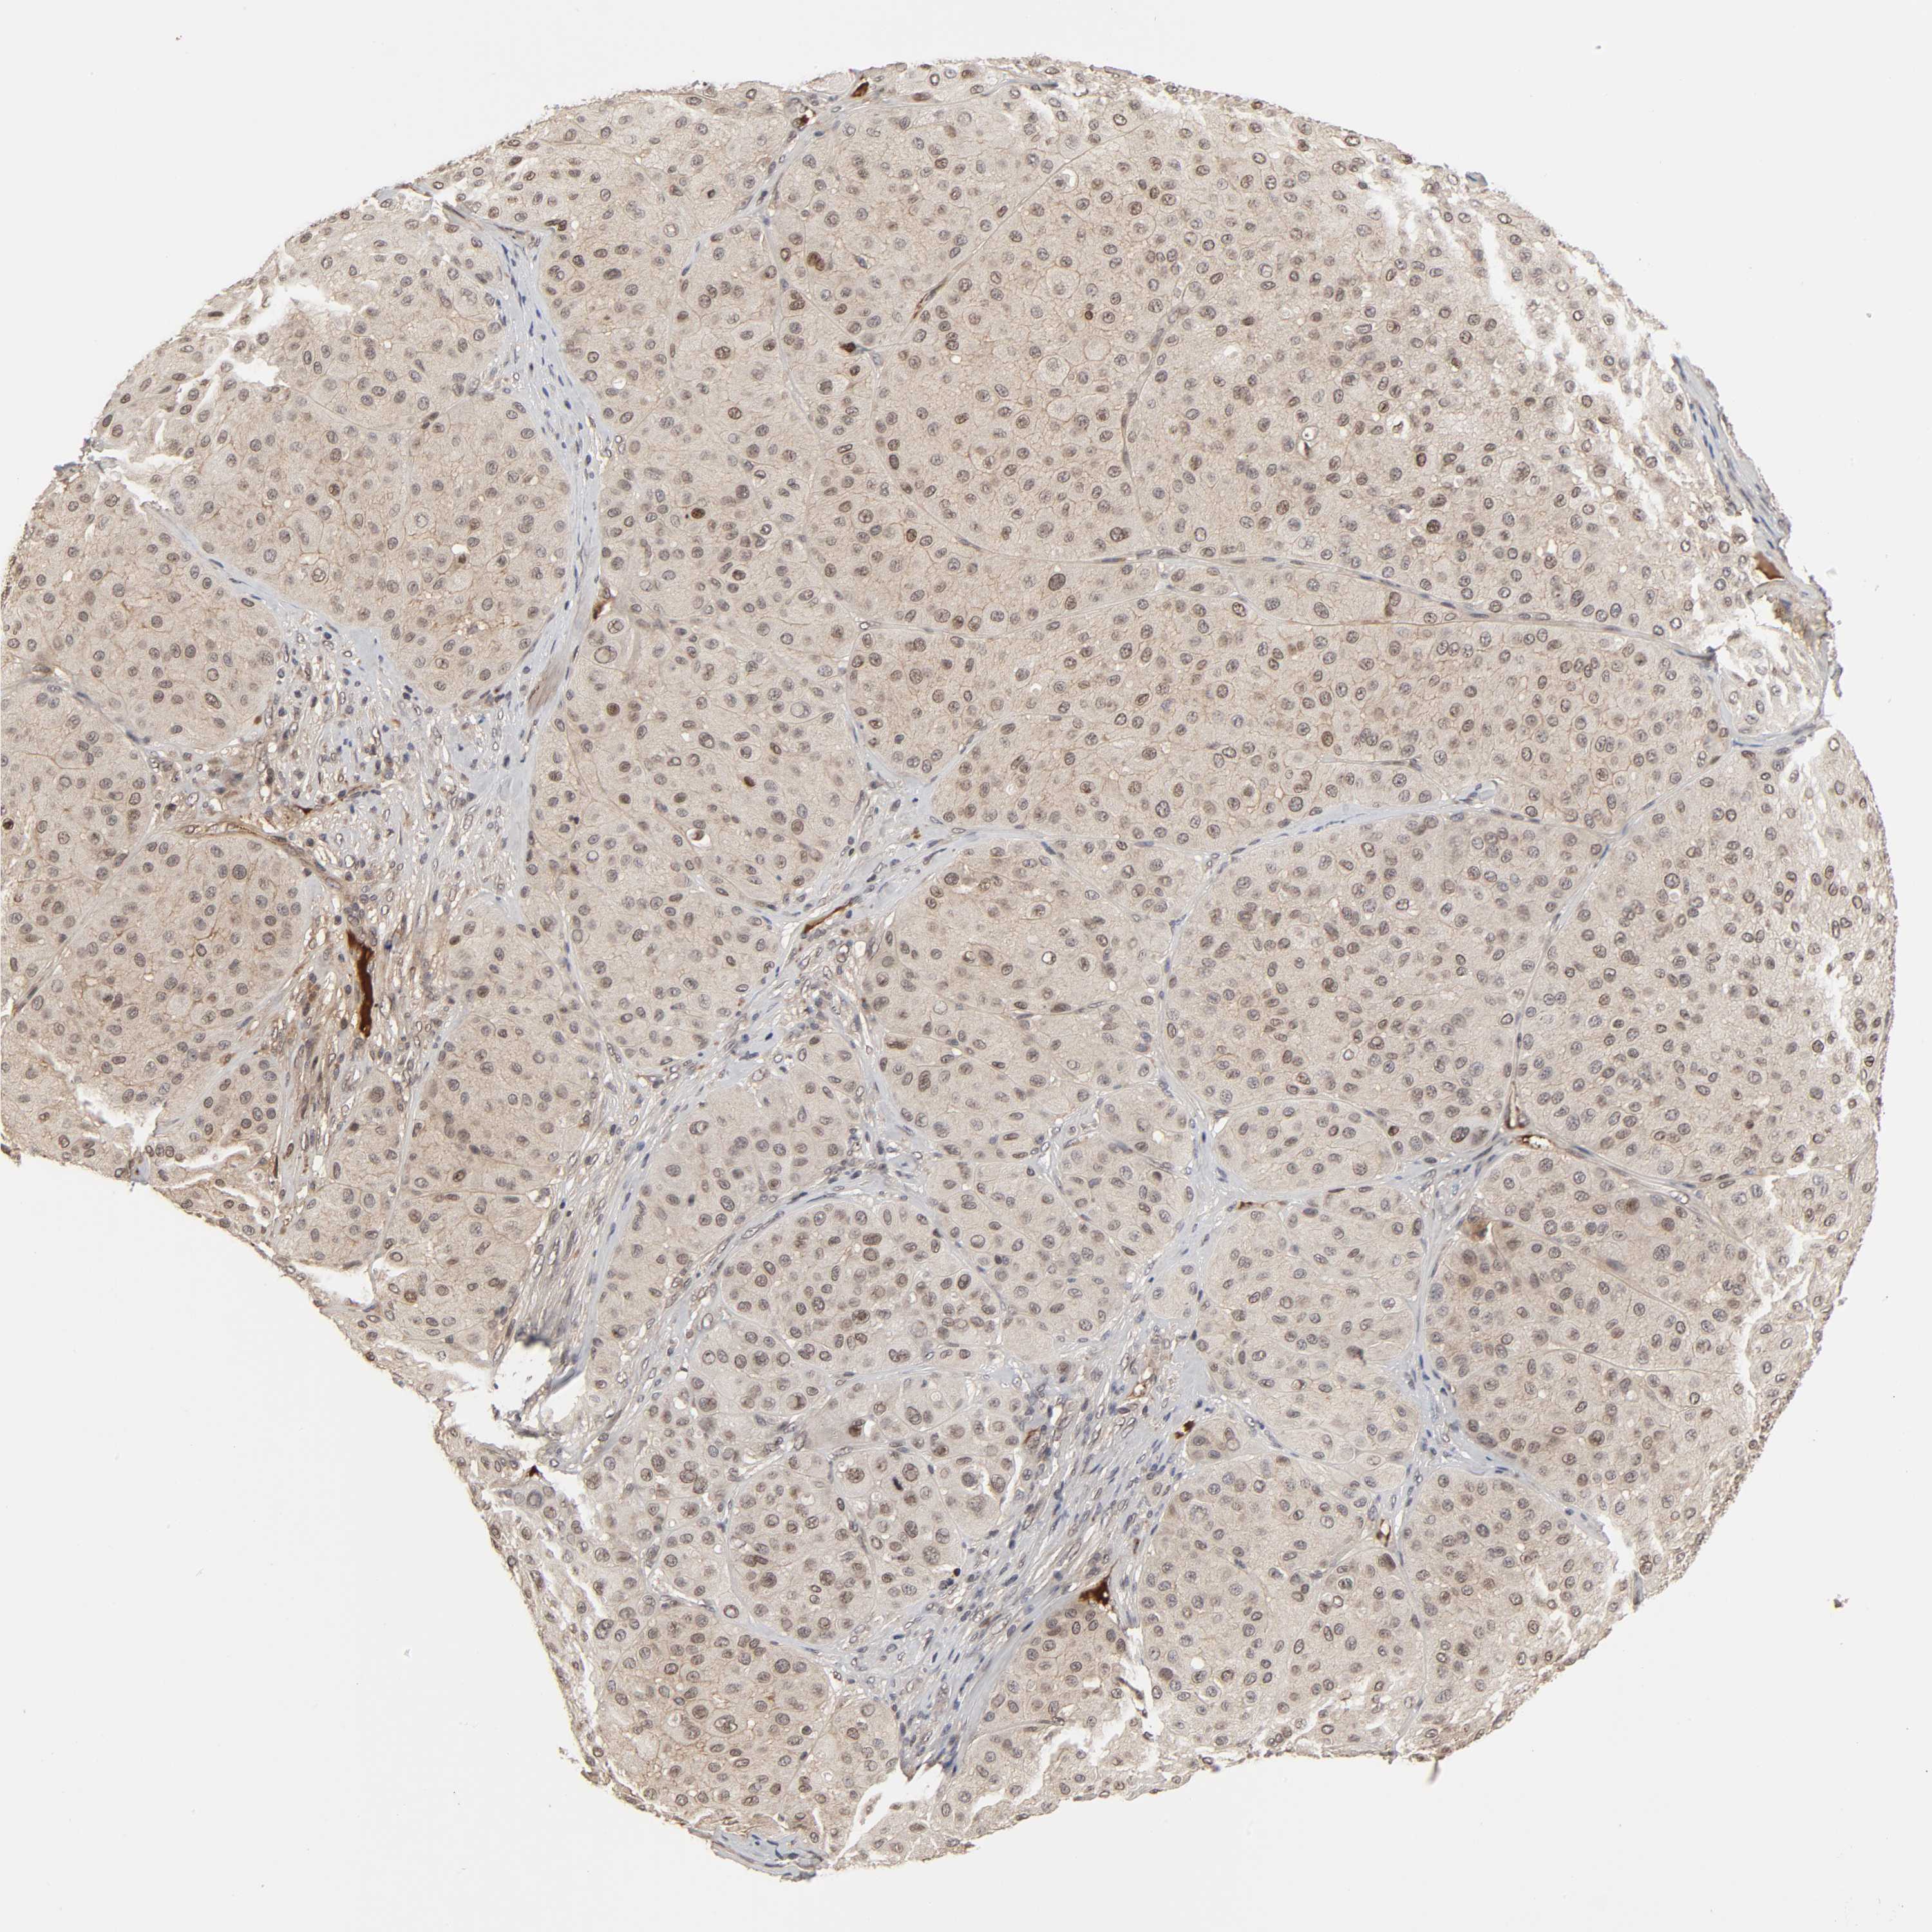

MELANOMA - Protein expressioni

A mouse-over function shows sample information and annotation data. Click on an image to view it in a full screen mode. Samples can be filtered based on level of antibody staining by selecting one or several of the following categories: high, medium, low and not detected. The assay and annotation is described here.

Note that samples used for immunohistochemistry by the Human Protein Atlas do not correspond to samples in the TCGA dataset.

Antibody stainingi

Antibody staining in the annotated cell types in the current human tissue is reported as not detected, low, medium, or high, based on conventional immunohistochemistry profiling in selected tissues. This score is based on the combination of the staining intensity and fraction of stained cells.

Each image is clickable and will lead to virtual microscopy that enables deeper exploration of all samples and also displays staining intensity scores, fraction scores and subcellular localization as well as patient and tissue information for each sample.

Antibody HPA004732

Staining

High

Medium

Low

Not detected

Intensity

Strong

Moderate

Weak

Negative

Quantity

>75%

75%-25%

<25%

None

Location

Nuclear

Cytoplasmic/membranous

Cytoplasmic/membranous,nuclear

Malignant melanoma, NOS

Malignant melanoma, Metastatic site